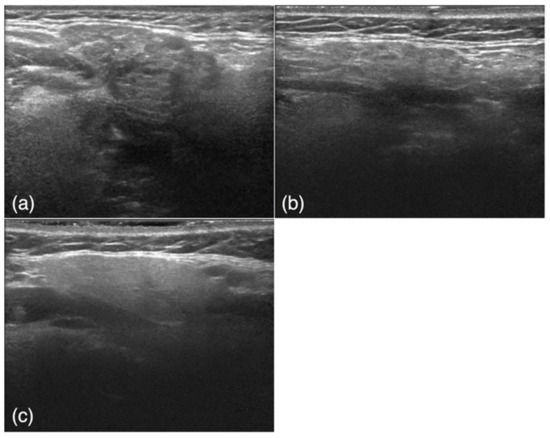

The subjects were retrospectively selected from an image database of patients who visited our institution from June 2010 to October 2019. The study included 50 USG images of 50 patients (26 men, 24 women; average age, 46.3 years) with SMG obstructive sialoadenitis confirmed by the presence of sialoliths using CT with inflammatory symptoms such as swelling and tenderness (obstructive sialoadenitis group) and 50 USG images of 28 patients (1 man, 27 women; average age, 66.0 years) with a confirmed diagnosis of SjS according to both the Japanese criteria [28] and the American–European Consensus Group criteria [29] (SjS group) (Figure 1a,b). The diagnosis of SjS was based on a blood test, sialography, and a Saxon test; in some cases, a biopsy was also performed if the above tests were inconclusive. Images of the affected side were obtained for patients with sialolithiasis, and images of both sides were obtained for patients with SjS. Among the obtained SjS images, six poor-quality images were excluded. USG scans were also obtained from 50 control subjects (26 men, 24 women; average age, 59.0 years) with no SMG abnormalities who had presented with other diseases, such as cervical lymph node metastasis of oral cancer or submandibular lymphadenitis (Figure 1c). The control subjects were randomly selected from the imaging database of our hospital retrospectively. The 150 images were randomly divided into training and test groups for the deep learning process. The training group comprised 40 images from the obstructive sialoadenitis group, 40 images from the SjS group, and 40 images from the control group. The test group comprised 10 images from the obstructive sialoadenitis group, 10 images from the SjS group, and 10 images from the control group.

Figure 1.

Examples of ultrasound images. (a) A patient in the obstructive sialoadenitis group shows inhomogeneous parenchyma and well-defined margins. (b) A patient in the Sjögren’s syndrome group shows inhomogeneous parenchyma characterized by multiple diffuse anechoic regions and ill-defined margins. (c) A patient in the control group shows homogeneous parenchyma and well-defined margins.